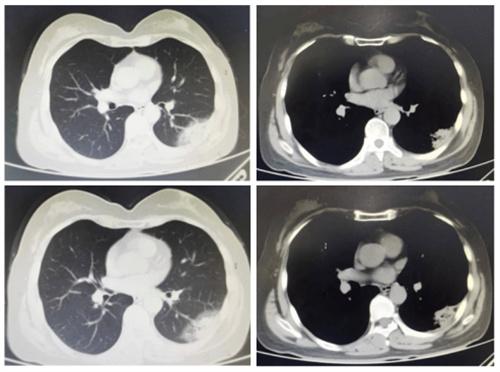

患者作為急性發熱,白細胞和炎癥指標都有升高,醫生考慮到很可能是細菌感染的可能性,三代頭孢是廣譜類的抗菌藥物,但在該患者身上卻并沒有用,當時做胸部CT后,突然發現肺部有肺炎。